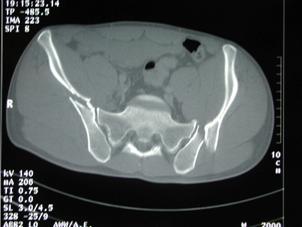

Fractura Malgaigne Fractura Malgaigne. Imagine CT

Fractura de

aripa iliaca stanga  Fractura de aripa iliaca

stanga

Disjunctie sacro-iliaca stanga Disjunctie

sacro-iliaca stanga Aspect CT